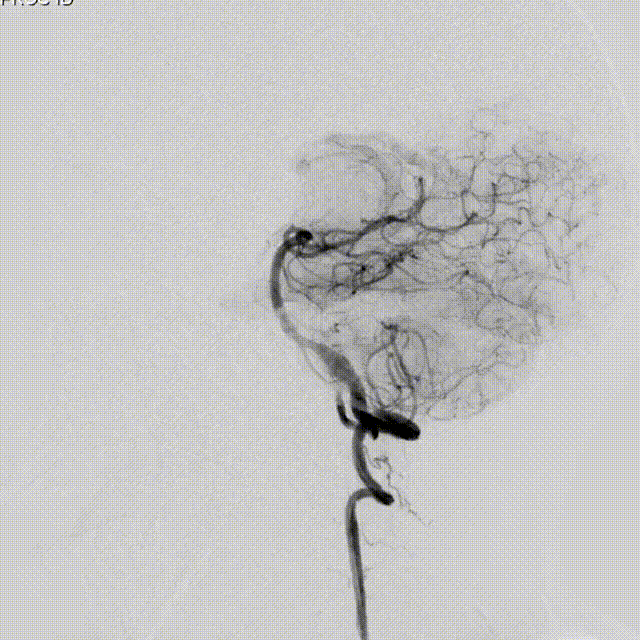

术后即刻造影:

造影确认支架打开贴壁良好。

继续释放支架中段。

Lattice支架完全释放:

解脱前造影。

撤微导管完全释放。

Lattice支架后处理:

J型导丝按摩。

术后即刻造影。